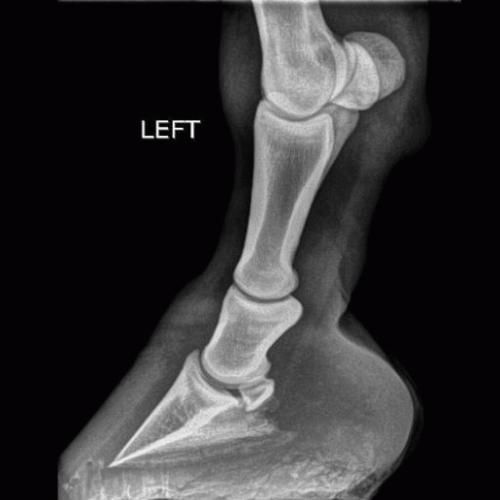

Nos gusta realizar trabajos de calidad, por lo que disponemos de todo tipo de equipamiento de última generación como radiología digital, ecografía de alta resolución y hematología y bioquímica en el acto. Trabajamos con laboratorios especialiazados en équidos para

ofrecerles las técnicas más fiables en métodos de diagnóstico.